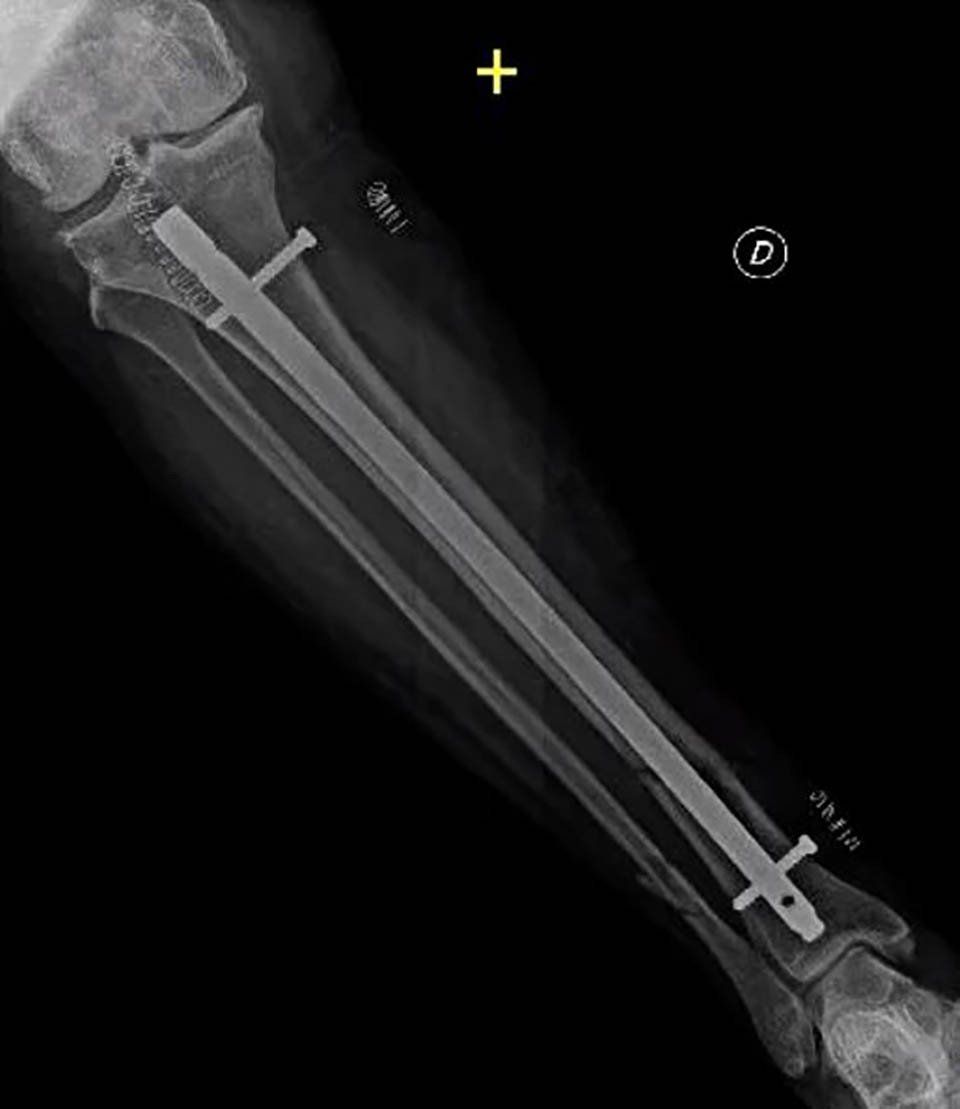

All non-surgical or surgical treatments for bone repair follow a basic rule: the fractured bone segment must be realigned, and the movement of the two fragments must be limited until complete healing. Some fractures, especially if complex, can be held in place with casts or splints; others require more stable surgical fixation, which can be achieved with intramedullary nails, plates, screws, or external fixators.

- Internal fixation: Orthopaedic surgeons use intramedullary nails, metal plates, and screws to stabilise pseudoarthrosis. Often, bone grafts are used to assist stability and promote healing.

- External fixation: Orthopaedic surgeons apply an external device to the affected limb using steel wires and pins. This method is preferred for pseudoarthrosis without sufficient stability, infected cases, or those with bone loss.